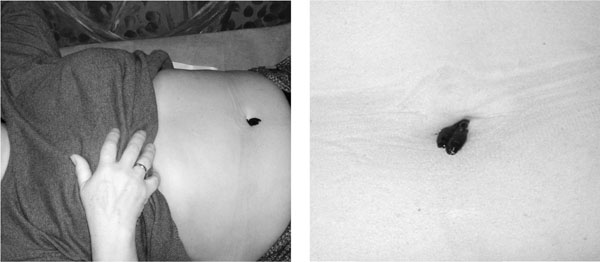

Пришла пора помочь печени. Поэтому вначале – очистка нашего главного «фильтра». И это не все – за первый курс мы вернемся в эту область и еще несколько раз поддержим тот процесс, который запустили в печени. Первый раз ставим всего одну-две пиявки в пупок. От пупка в печень идет воротная вена – большая часть слюны пиявки попадает в печень. Это «анатомическая» постановка для очистки печени. Именно так рекомендует начинать курс гирудотерапии Сухов Константин Васильевич, кандидат медицинских наук, практикующий врач, вице-президент Российской профессиональной медицинской ассоциации специалистов традиционной и народной медицины. Чем хороша такая постановка? Нет следов от укуса – никто их не увидит, они постепенно рассосутся бесследно. Пациент не боится двух пиявок – нет стрессовой реакции на первую постановку. У нас с вами есть возможность оценить качество крови в печени – как увеличились пиявки за 45 минут? Смогли ли они насытиться и сами отвалиться? Остались такие же маленькие? Значит, кровь печени слишком вязкая, они устали и не успели поесть, много пришлось отдыхать, не хватило слюны для разжижения такой крови. Печень «забита», гормоны плохо контролируются, эндокринология «хромает» – у нас много работы, надо включать все в комплексе и строго следить за выполнением рекомендаций. Если к тому же пациент жалуется на горечь во рту (спросите его об этом) и при пальпации печень выпирает за край правой реберной дуги – отправляйте на УЗИ брюшной полости посмотреть, не увеличена ли печень. Возможно, придется не просто чистить и активировать печень, а снимать ее конкретный диагноз, о котором пациент и сам не знал, например гемангиому печени, которая может бессимптомно расти, если на нее не обращать внимание. Надеяться, что удастся привести в порядок организм, «слепо» поставив пару пиявок в пупок, не стоит – слишком многое зависит от печени. Поставить пиявочки очень просто: возьмите шприц 5 мг в аптеке, срежьте иглу и обработайте край мелкой наждачкой, чтоб не царапался. Посадите две пиявки в шприц и слегка нажмите клапан, оставив пиявочкам место, но подвинув их поближе к коже. Вы увидите, как они «встали».

Если какая-то не хочет садиться, придется поменять ее – это живые существа, и вполне возможно, что им может не нравиться запах кожи и пота, они не чувствуют сегодня желания есть эту еду – найдем более «сговорчивую», а ту посадим в другой раз. Я всегда грею перед постановкой место укуса 5–10 секунд – пока сажаю пиявки в шприц, на коже пациента в нужном месте лежит отжатый ватный диск, смоченный в горячей воде. Пиявка любит теплое и меньше капризничает. У меня в «арсенале» несколько подготовленных шприцев разного диаметра – для разных мест. Пиявки не любят очень тесного пространства, но иногда надо поставить более точно. Стараемся поставить в пупок прямо в серединку, но не расстраиваемся и не снимаем пиявочку, если она встала немного сбоку в пупочке – там вся зона рабочая. Больше часа держать не стоит – все, что могла, она для вас сделала – всю слюну впрыснула, теперь эта слюна будет работать, и на следующий раз в эту зону другие пиявки встанут более охотно, быстрее наедятся и продолжат начатое сегодня. За один раз не почистить то, что копилось годами. Будем терпеливы. Через 45–60 минут можно снять пиявку. В место укуса вставляем свернутый в трубочку ватный диск, а сверху еще два-три диска или кусочек прокладки.

Постановка пиявки пациенту в пупок